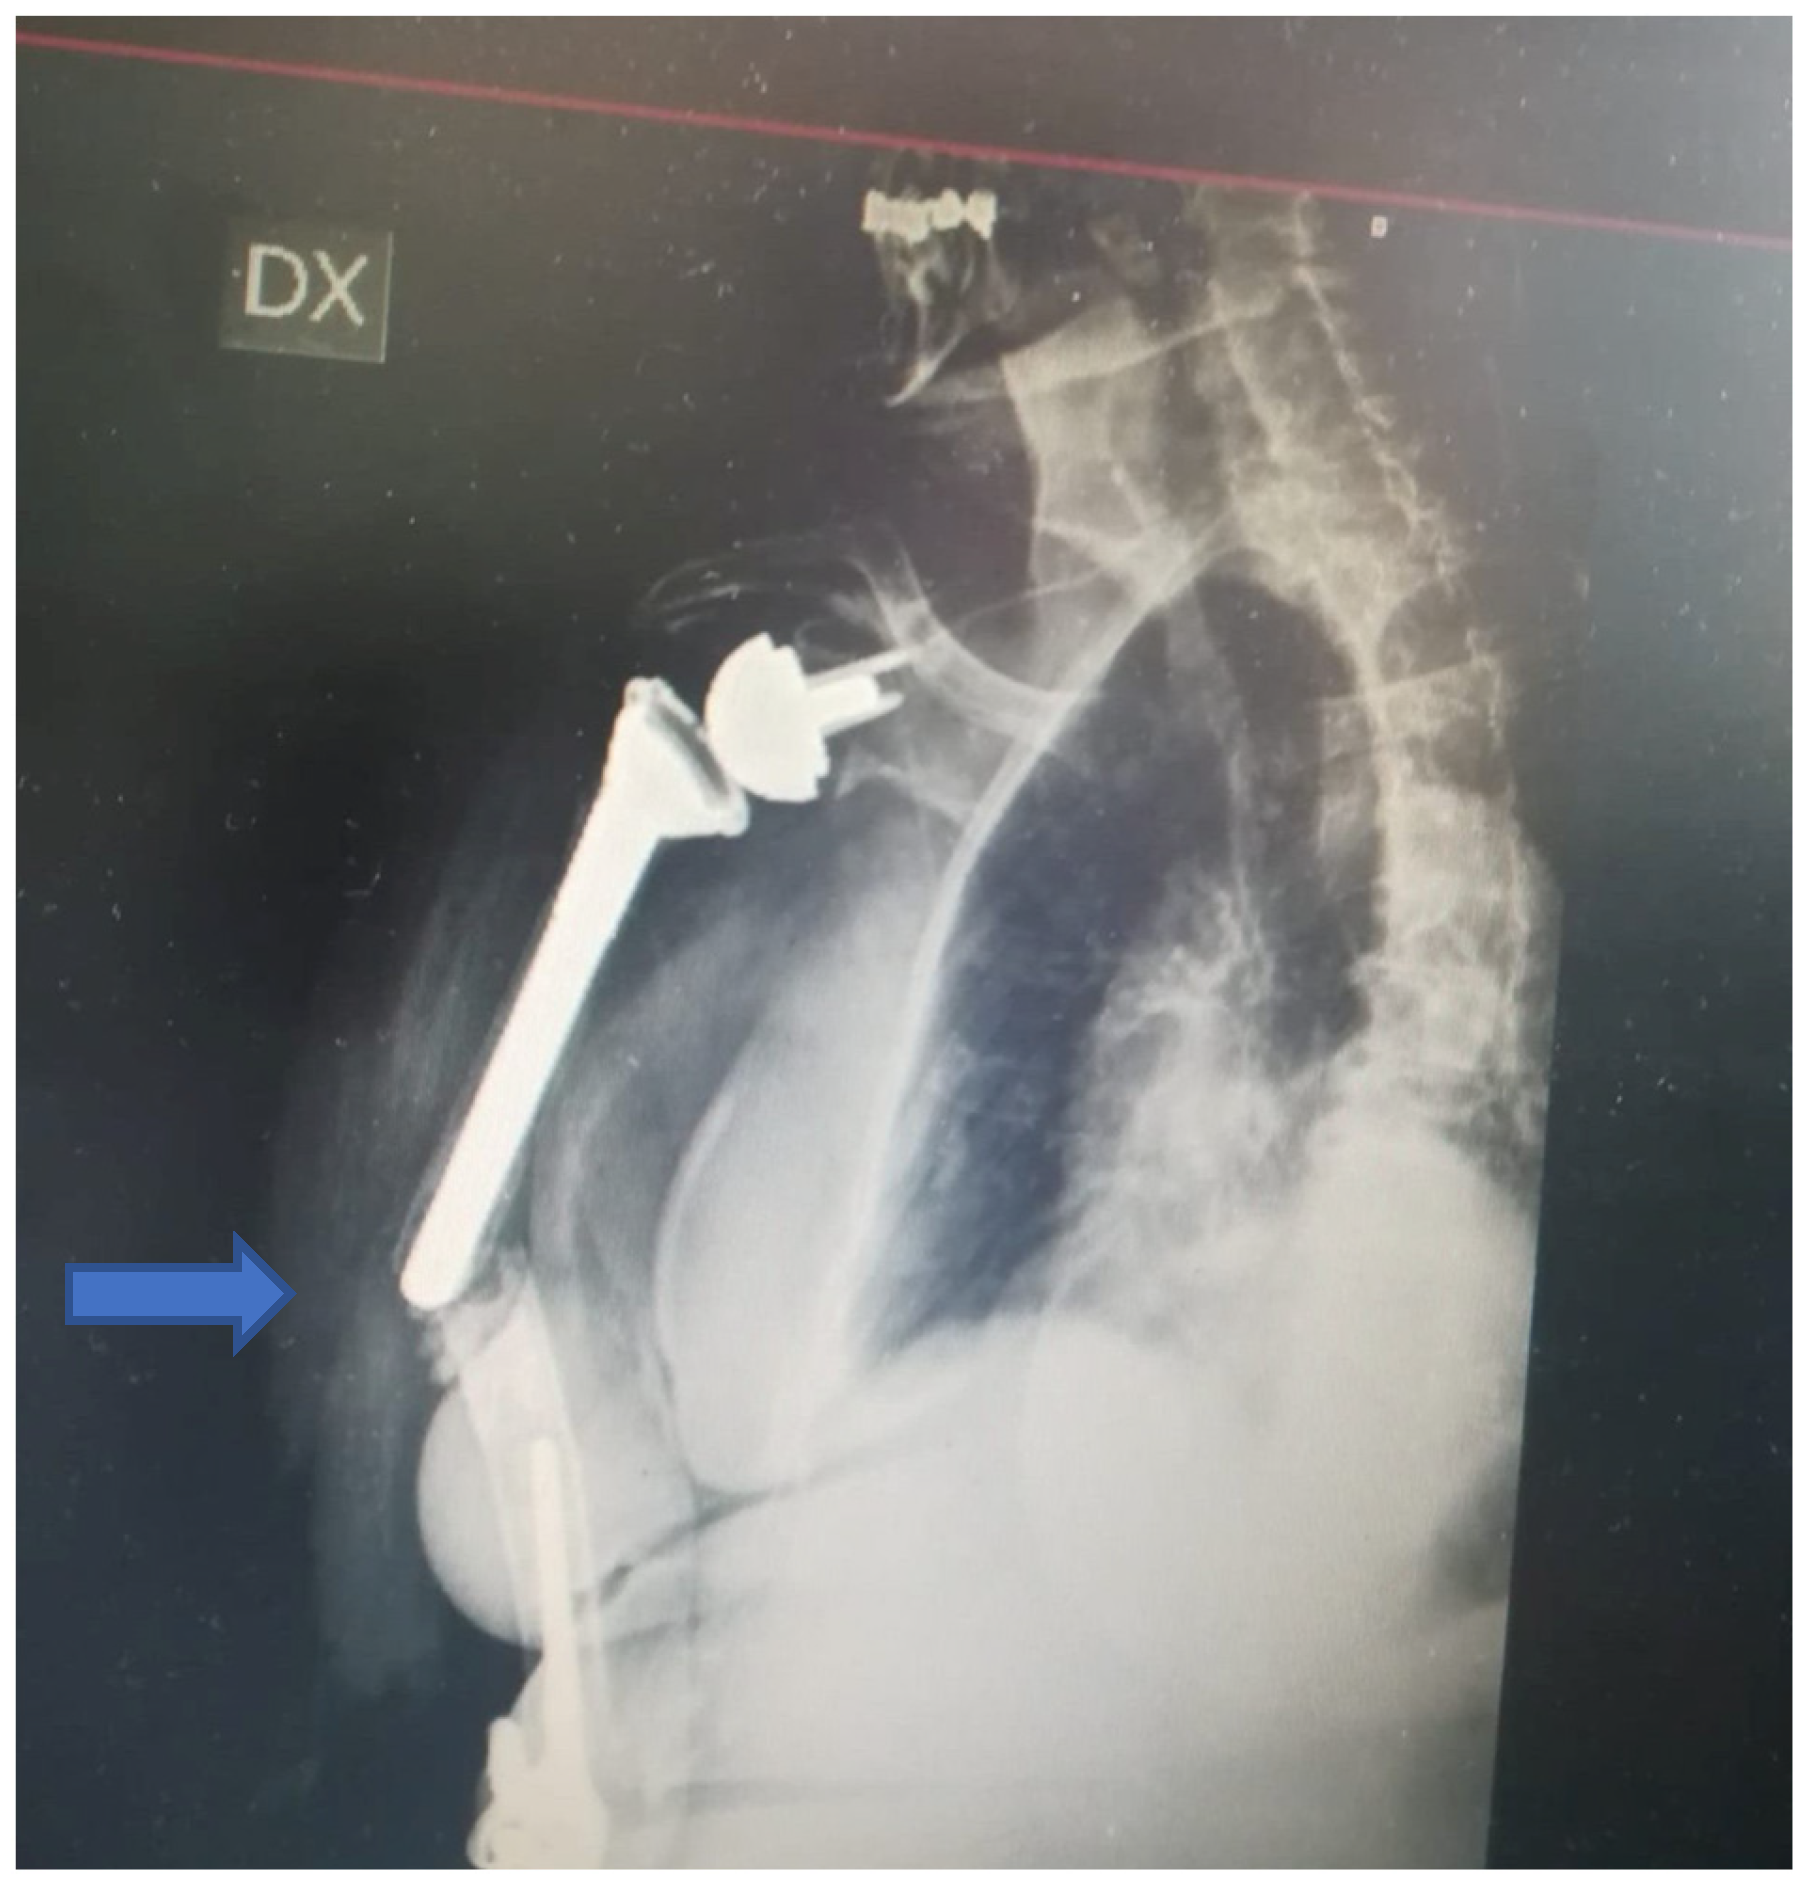

A 76-year-old woman was transferred from a primary general referral centre to our secondary Trauma and Orthopaedic Department referral centre after sustaining a low-energy fall. She fell onto the right side when at home. The patient’s medical history included several comorbidities: type II diabetes mellitus, severe osteoporosis, hypertension, hypercholesterolemia and hyperuricemia, complex treated trauma to her right shoulder and elbow (2010 and 2012), respectively, with reverse shoulder arthroplasty and total elbow arthroplasty (at a different orthopaedic trauma centres).On admission, plain radiographs of the right arm showed an IHF between the two stemmed prostheses (Figure 1).

Figure 1.

X-ray at admission. Complex fracture between a stemmed cemented reverse shoulder arthroplasty and elbow arthroplasty associated with severe bone loss.

The fracture occurred at the shoulder’s stem tip without compromising the stability of the arthroplasty associated with cement leakage. The fracture was classified as type D according to the Unified Classification System (UCS) [7]. Type D is a fracture affecting one bone which supports two replacements, such as the humerus following shoulder and elbow replacement, or the tibia following knee and ankle replacement. [7] The shoulder prosthesis was a reverse implant with a cemented stem, whilst the elbow arthroplasty was an uncemented Conrad Moore implant. Moreover, a severe poor bone stock was noted around the fracture site. Clinical examination revealed a high level of right arm pain and tenderness; a vast ecchymosis without any skin lesion and no signs of vascular or neurological injury were noted. The vital signs and the laboratory results were in the normal range despite the several comorbidities. The literature related to the management of such injuries was reviewed within the local Trauma and Orthopaedic Department, and the case was discussed at the local multidisciplinary meeting: The decision to proceed with surgical management was agreed upon (in agreement with the patient), and the treatment strategy consisted of open reduction, internal fixation with plating and cerclage, and xenografting from the equinus femur and biological bone grafting with adjunct growth factors in case of poor bone quality and stock. One week after the admission (after having held the aforementioned meetings and after the arrival of the surgical instrumentations and the graft), the patient underwent the planned surgical procedure (Figure 2).